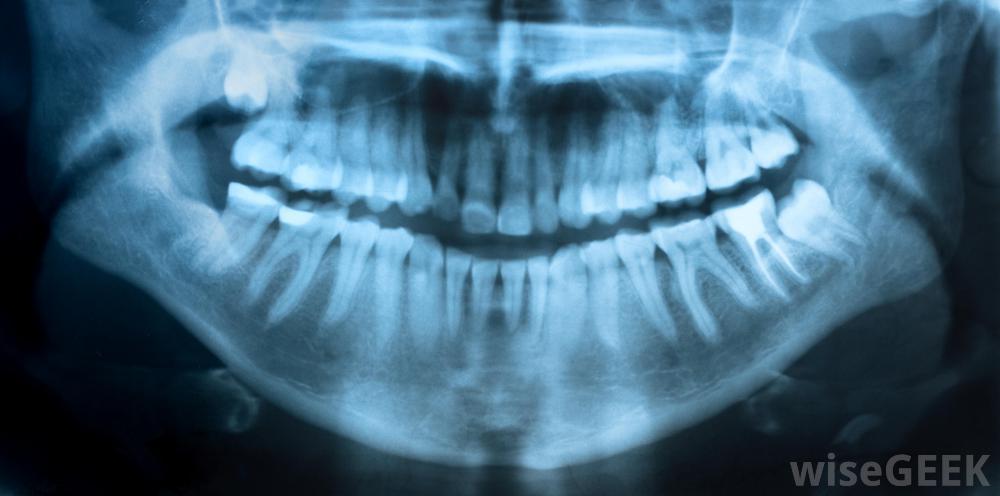

一些牙齿问题是通过x光片检测出来的细菌性蛀牙,称为龋齿,通过牙齿外层扩散感染牙髓,通常是牙髓炎的原因,但并不总是。对感染或创伤的免疫反应通常包括更大的血液流向该区域,因此称为淋巴细胞的白血球可以到达该部位,并且淋巴细胞和其他细胞释放的化学物质会导致炎症。根据肿胀的严重程度,可能会引起不同程度的疼痛。在某些情况下,患有这种情况的人可能不会有任何疼痛,但在另一些情况下,可能会感觉到与血液到达该区域时相一致的剧烈搏动疼痛,同时对温度有更高的敏感性

有些牙髓炎患者可能会出现剧烈的搏动疼痛当不可逆牙髓炎发生时,它通常会引起疼痛,在扳机被取下后,疼痛会持续10秒。像这样无法修复的损伤有时可以通过电子手段或x光来检测到。这种情况没有真正的治疗方法,所以通常情况下,牙髓必须为了使人得到缓解而完全拔除。有时可以进行根管切除牙髓,但在极端情况下,可能需要拔除整个牙齿

不可逆性牙髓炎可能导致轻度疼痛和对冷热液体的敏感性牙髓炎可以通过x射线检测或确认。